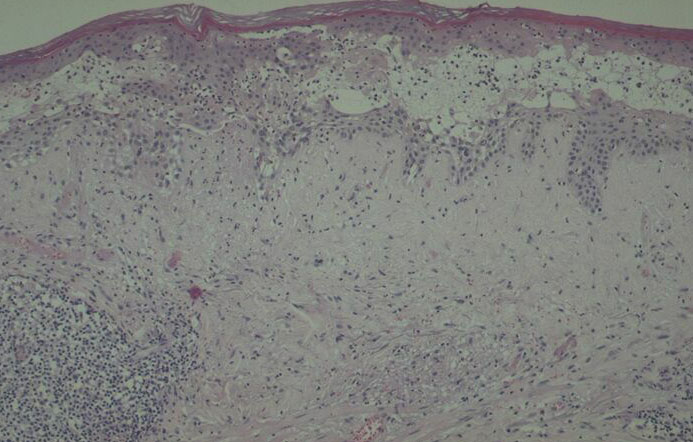

Histology. The main, very characteristic, histologic abnormality is that of progressive intra- and intercellular epidermal edema leading to prominent reticular degeneration, vesiculation, and finally confluent epidermal necrosis . The vesicles contain fibrin and acute inflammatory cells and overlie a dermal cellular infiltrate of predominantly perivascular lymphocytes, histiocytes, and neutrophils . A vasculitis is not seen. In some cases, there is focal necrosis of the superficial dermis. Prominent secondary changes in late lesions may obscure the characteristic findings. |